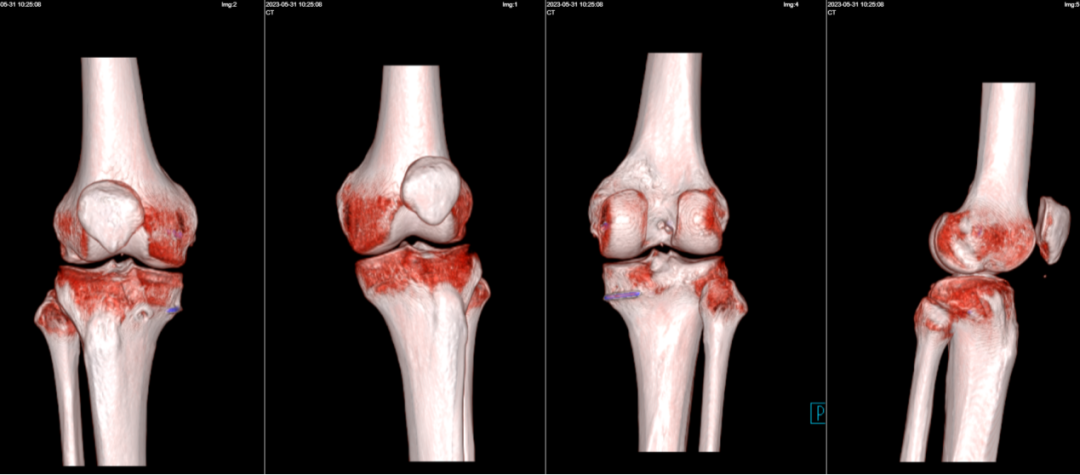

*术后复查X片

6月2日,高玉镭主任为患者实施“股薄肌、半腱肌、腓骨长肌取腱术+关节镜下右膝前交叉韧带重建翻修术+半月板缝合术”,术中所见:前交叉韧带部分断裂、松弛,韧带内淤血,外侧半月板后角撕裂。高玉镭主任介绍说:“手术过程中,刨削器刨除关节内积血,彻底止血。给予缝合外侧半月板后角。然后,于胫骨结节内侧取出两条肌腱,于右踝关节外侧切口内取1/3腓骨长肌肌腱,并在工作台上对其预处理,接下来才是相关重建流程。整个手术过程比较复杂,但彻底解决了手术后各种并发症隐患。”